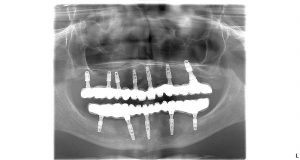

Tamaru trápil stav jej chrupu dlhodobo. V hornej čeľusti mala všetky moláre nahradené mostíkmi ktoré boli v nevyhovujúcom stave. V spodnej čeľusti mala už len 9 zubov a preto žuvacia schopnosť bola značne narušená.

Plán ošetrenia od MUDr. Salku znel:

Vrchná čeľusť: 8 extrakcií, 7 zubných implantátov, 14 – členný keramický mostík

Spodná čeľusť: 9 extrakcií, 5 zubných implantátov, 14 – členný keramický mostík

Celé ošetrenie si vyžadovalo 3 návštevy na klinike. Po konzultácii si pacientka rezervovala termín na zavedenie zubných implantátov. Zubné implantáty sa zaviedli do oboch čeľustí pri jednom sedení. Na zavedené zubné implantáty sa fixne nasadili dočasné zubné mostíky z titánovou konštrukciou, ktoré vám zabezpečia okamžitú náhradu zubov. Hojenie zubných implantátov trvá 2-3 mesiace. Počas doby hojenia je potrebné, aby pacient konzumoval mäkkú alebo tekutú stravu. Zubné implantáty nesmú byť zaťažované žutím. Zapríčinilo by to komplikácie pri hojení a vylúčenie zubných implantátov.